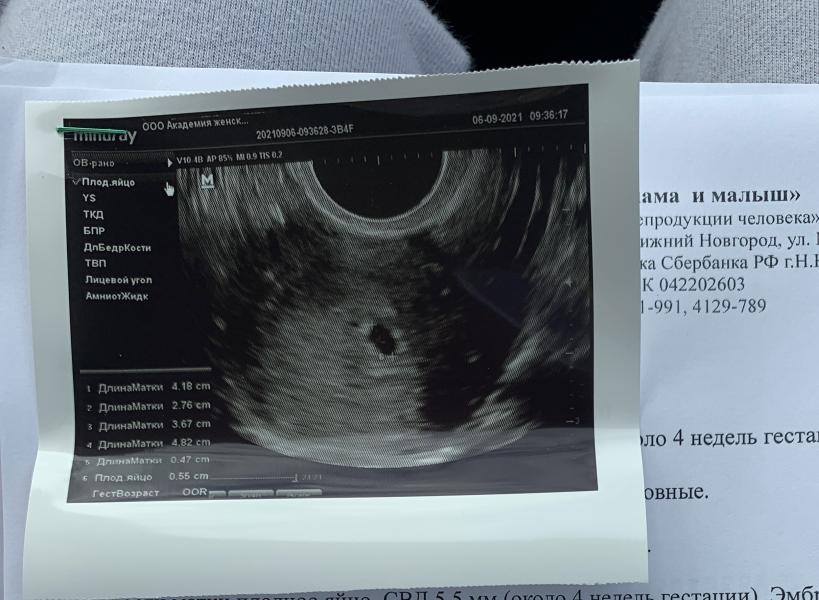

Но врач мне ничего не сказала, посмотрела лишь и увидела плодное яйцо в правой трубе

Сдала хгч в тот же день.

Пришёл результат : 2106

Звоню доктору, та в шоке. «ого, это много, должно было уже опуститься»

Я реву, говорю как так, это что значит внематочная?

«Скорее всего да, если будут боли не терпи и вызывай скорую»

Пошла к репродуктологам

Там меня осмотрели аж три врача 😁 со сло...